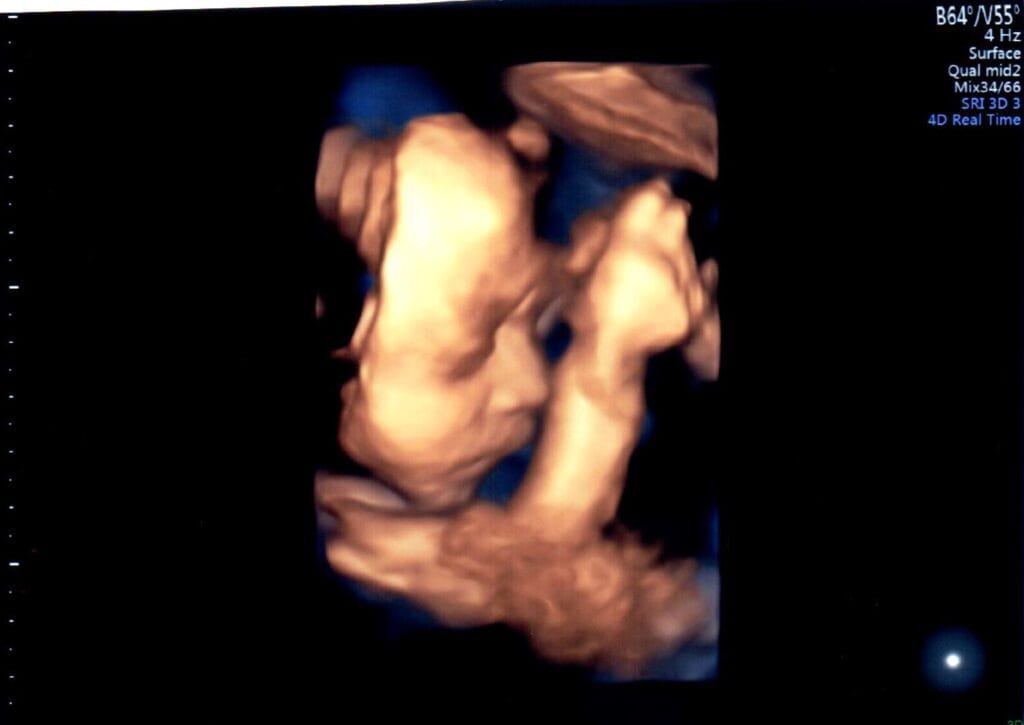

妊婦健診時に3D・4D超音波を行っています

妊婦健診の超音波測定で、赤ちゃんの様子がわかる3D・4D超音波を行っています。

胎位により、3D・4D画像がうつりにくい場合がありますので、週数時期については、技師にお任せください。

ご理解の程、よろしくお願いいたします。

胎位により、映り方には個人差があります。